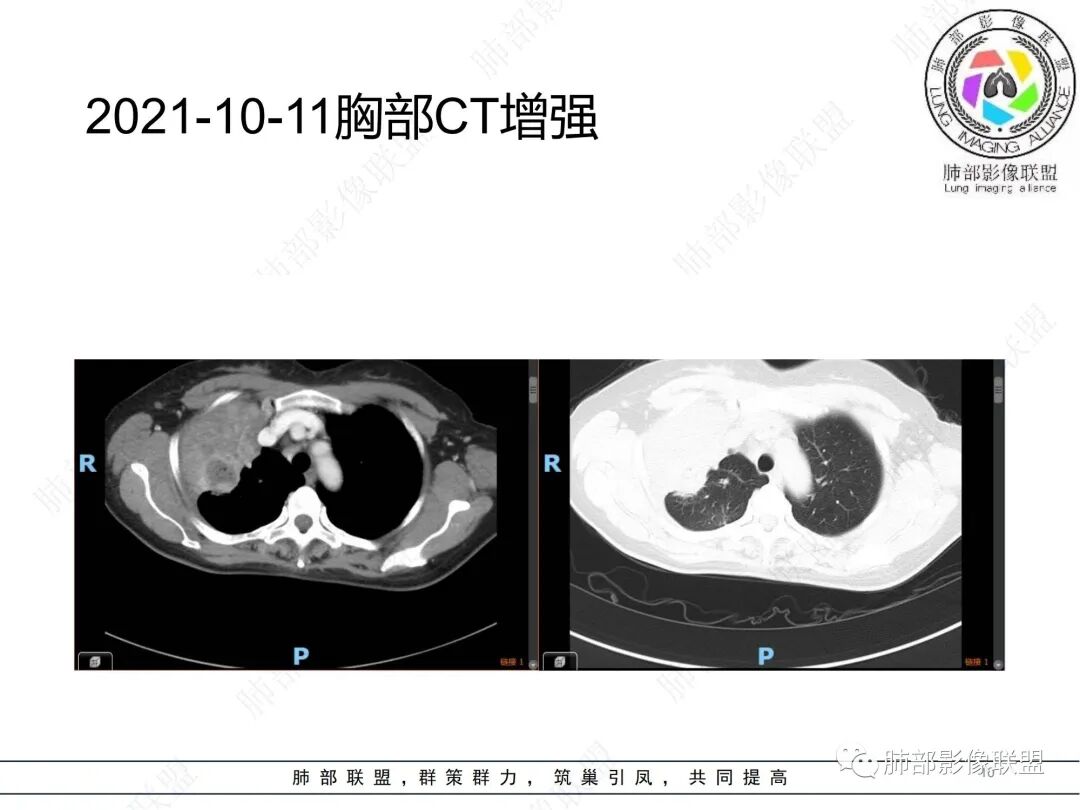

治疗前后对比CT:

放线菌病